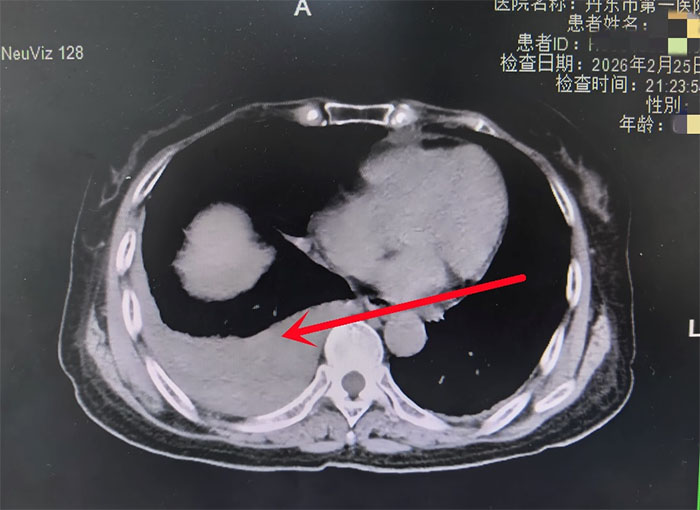

(箭头所指为血凝块) 时间就是生命!我院胸外科副主任李林当机立断,带领科室医疗团队立即进行急诊手术治疗。

当胸腔镜探入刘阿姨胸腔的那一刻,所有人都倒吸一口凉气:胸腔内充满了大量积血和血凝块。手术团队一边熟练清除血肿,一边寻找出血点。经过耐心细致的搜寻,终于找到了导致这一切危险事件的“致命真凶”——膈肌破裂。

原来,那场看似不重的摔倒意外,不仅撞断了肋骨,还撕开了一个微小的膈肌裂口。这个裂口就像水管上的一个小洞,在初期不痛不痒,CT检查也难以发现。但它在持续缓慢渗血,最终导致大出血。更可怕的是,如果没有及时发现并修补,腹腔里的胃、肠子等器官随时可能从这个裂口钻进胸腔,挤压心脏和肺,一旦发生,死亡率极高。